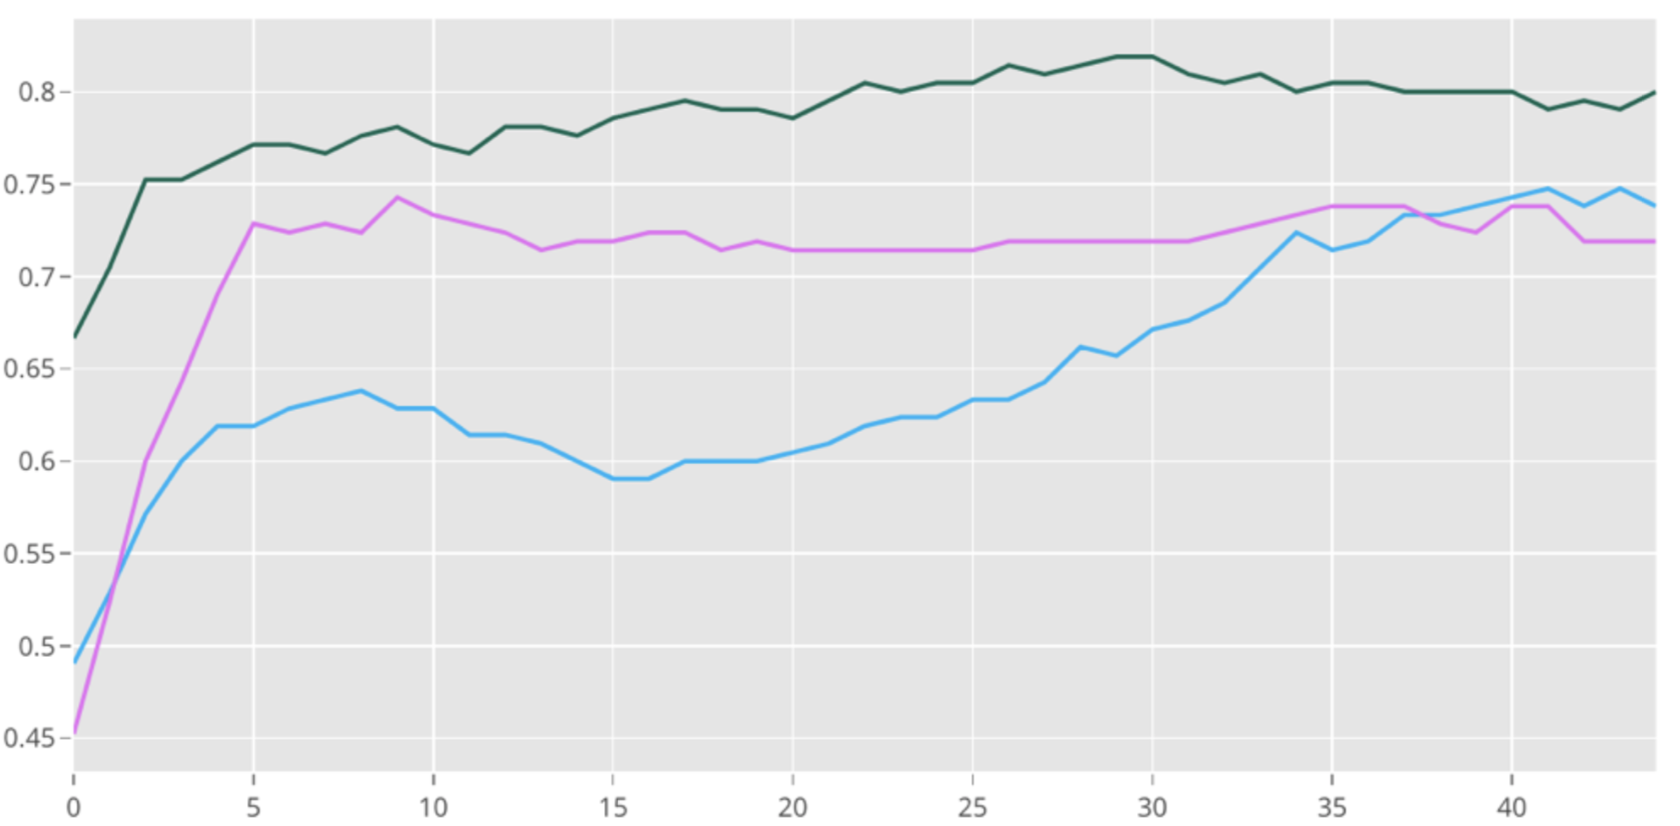

The multimodal on average improves accuracy efficiently by 4% and 7% compared to the baseline models which are an individual text model and an image model when fine tuned with learning rate . As show in Figure 5, shows the performance of our multimodal compared to two baseline models which are individual text model and image model on Indiana University dataset tuned with a learning rate of . The lines represent the mean accuracy and the spread represents the variance over the course of 10 stratified splits and 10 epochs. The bottom graph shows accuracy after tuning with a learning rate of . This yields a total dominance of the multimodal over the course of 50 epochs.

The experiments of over 10 stratified splits of the data yielded the following average results for multimodal and its stand alone submodals with high learning rates over 10 epochs. The low learning rate experiments were done with 3 stratified splits over 50 epochs.